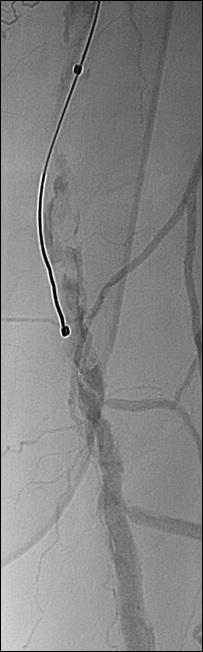

n PERIPHERAL ARTERIAL DISEASE:

Crossing chronic total occlusion lesions are challenging procedures. The BeBack crossing catheter—Bentley’s first product to be available in both Europe and the USA following the company’s acquisition of Upstream Peripheral Medical Technologies’ GoBack crossing catheter in September 2022— offers a new solution in this space. In a Bentleysponsored advertorial, Andrej Schmidt (Leipzig, Germany) shares his clinical experience with the BeBack, noting how it has been a “gamechanger” in his endovascular peripheral arterial disease practice.

For more on this story go to page 19.